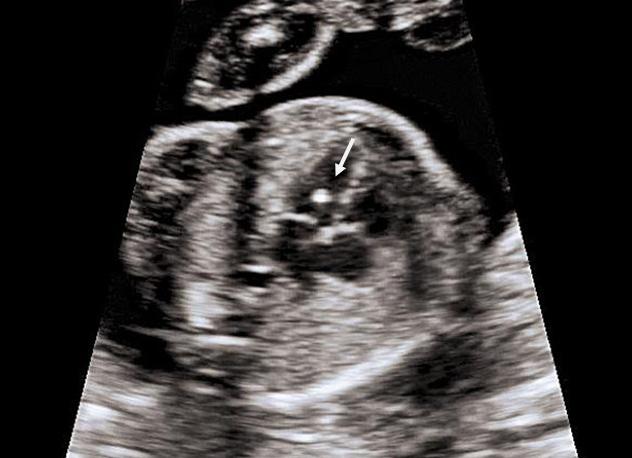

Гиперэхогенным фокусом называют округлое гиперэхогенное (сопоставимое по звукопроводимости с костной и фасциальной тканью) включение в проекции мышечного слоя сердца, диаметром не менее 2 мм, пропускающее ультразвуковые лучи.

Впервые он был описан в научной литературе профессором Линдси Аллан (Великобритания) в 1986 году, она дала ему название «мяча для гольфа», видимо, из-за ассоциации с этим мячиком ритмично подпрыгивающего в режиме реального исследования белого пятнышка. Частота встречаемости гиперэхогенного фокуса сердца плода в странах СНГ в среднем составляет 1-7%. Более часто он встречается у матерей возрастом старше 35 лет, азиатской расы.

Часто в заключениях специалистов УЗИ можно найти словосочетание «гиперэхогенное включение в проекции левого желудочка», что также отражает наличие гиперэхогенного фокуса. Это просто слова-синонимы. Гиперэхогенное включение может быть обнаружен в проекции любой из камер сердца, но чаще всего выявляют гиперэхогенный фокус в левом желудочке сердца плода.

гиперэхогенный фокус в левом желудочке сердца плода

Наиболее подходящий эхографический срез для поиска такого признака – срез через четыре камеры сердца.

Что означает наличие фокуса повышенной эхогенности в сердце плода? Для выяснения возможных последствий наличия такого фокуса в сердце плода для его здоровья было проведено множество различных исследований. Одно из них, мультицентровое, было выполнено в России в 1999 году, и на его основании можно сделать следующие выводы: наличие изолированного гиперэхогенного включения (фокуса) в сердце плода достоверно не является доказательством наличия хромосомных аномалий развития, его следует считать маркером хромосомной патологии только в случае наличия других маркеров и/или факторов риска.

Стоит учесть, что в большинстве случаев изолированный фокус повышенной эхогенности является отложением солей кальция в сердечной мышце или же утолщением эндокардиального аппарата. Также рядом зарубежных авторов были разработаны гипотезы о наличии хориальной ткани в проекции миокарда, дающей такой акустический эффект; о микрокальцификатах на месте ишемического повреждения миокарда, и пр.

Впрочем, все авторы сходятся в одном, что наличие фокуса повышенной эхогенности обусловлено патофизиологическими, а не генетическими причинами.